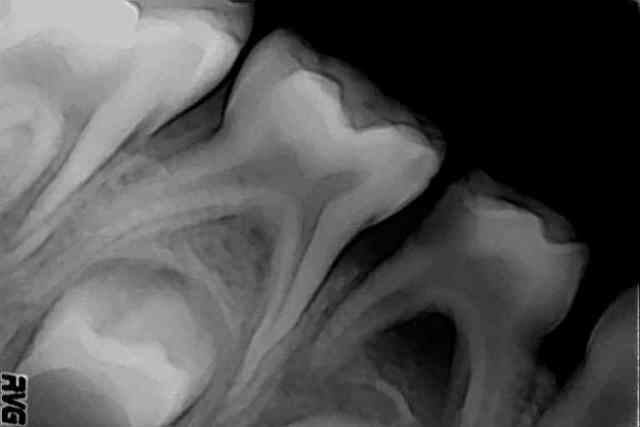

les voila les radios...

84 abces gosse de 6 ans... la question était est-ce qu'on peut garder la dent et comment... souvent qd on a un abces on a une atteinte de furcation.. qui extrait et qui garde?

finalement j'ai laissé ouvert puis obturé à l'hydroxyde de calcium qq jours plus tard...